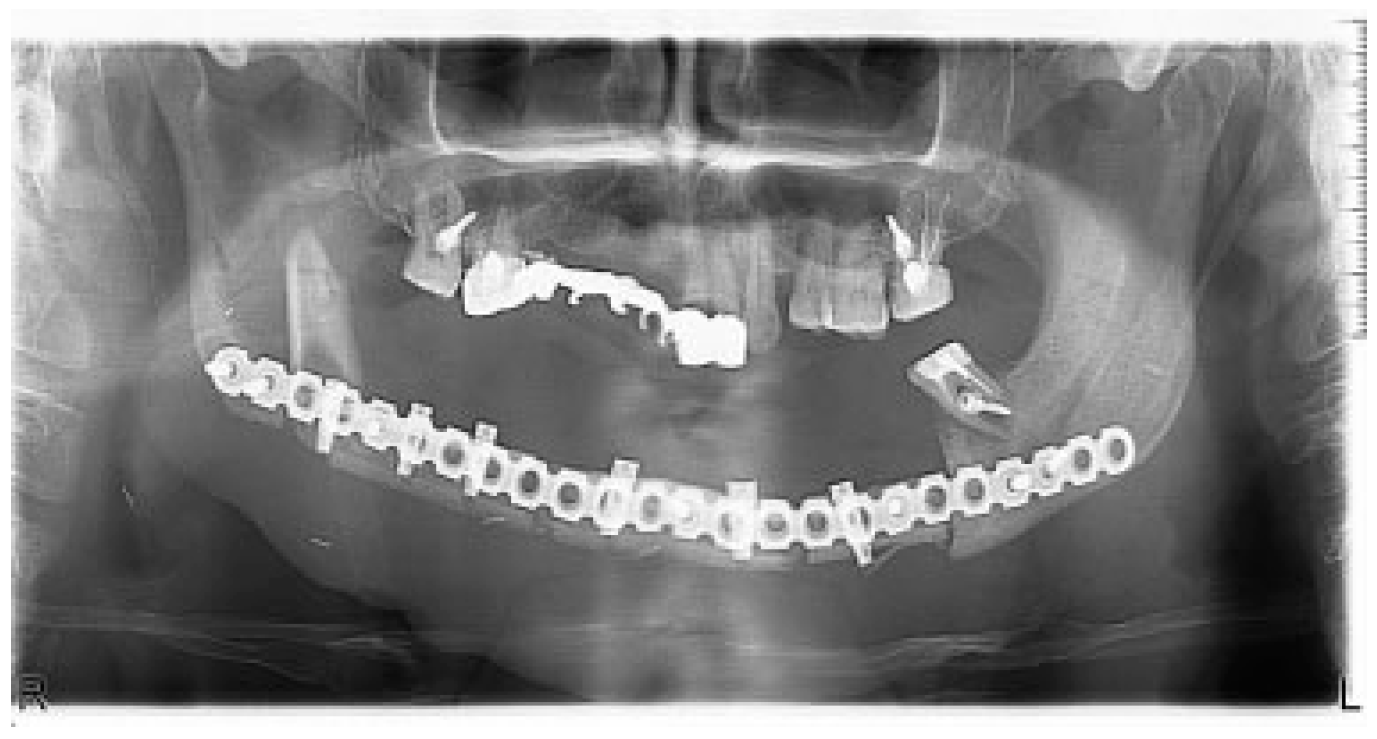

There were no significant complications postoperatively. Postoperative CT and OPG showed bone graft, dental implants, and reconstructive plate to be positioned in accurate anatomical relationship to each other and facial skeleton (Figure 8). A half year later, reconstructive plate was replaced by titanium miniplates (Figure 9).

Figure 8. Postoperative radiology: OPG.